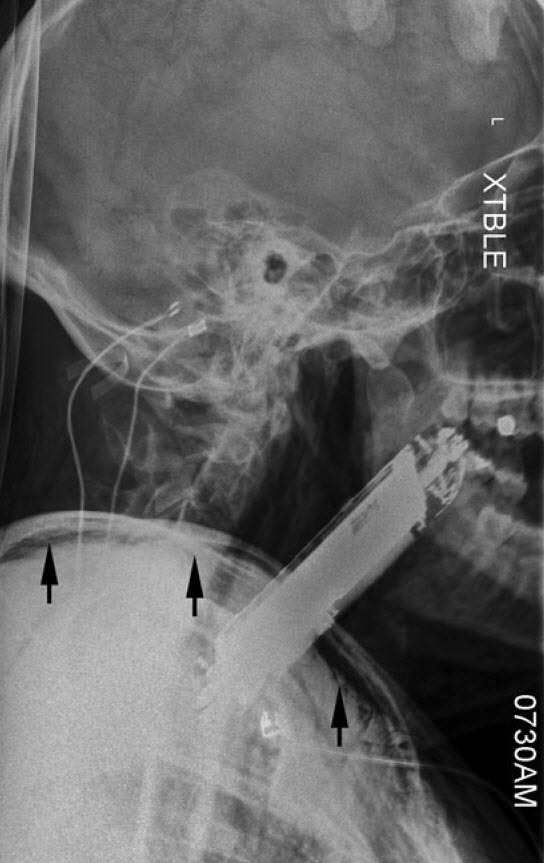

تحت تأثیر این توهمها، او گوشی هوشمند خود را که ابعادش ۴ در ۸ سانتیمتر بود، بلعیده بود!

گوشی موبایل به وضوح وارد حلق (اوروفارنکس) او شده بود و این قسمت را به جلو منحرف کرده بود. سرعت تنفس او بالا رفته بود و در هر دقیقه به ۲۴ تنفس رسیده بود. میزان اشباع اکسیژن او ۹۲ درصد بود و سرعت ضربان قلباش ۱۳۱ ضربه در دقیقه بود، فشار خونش هم ۱۳۷ روی ۶۴ میلیمتر جیوه بود.

تحت تأثیر این توهمها، او گوشی هوشمند خود را که ابعادش ۴ در ۸ سانتیمتر بود، بلعیده بود!

گوشی موبایل به وضوح وارد حلق (اوروفارنکس) او شده بود و این قسمت را به جلو منحرف کرده بود. سرعت تنفس او بالا رفته بود و در هر دقیقه به ۲۴ تنفس رسیده بود. میزان اشباع اکسیژن او ۹۲ درصد بود و سرعت ضربان قلباش ۱۳۱ ضربه در دقیقه بود، فشار خونش هم ۱۳۷ روی ۶۴ میلیمتر جیوه بود.